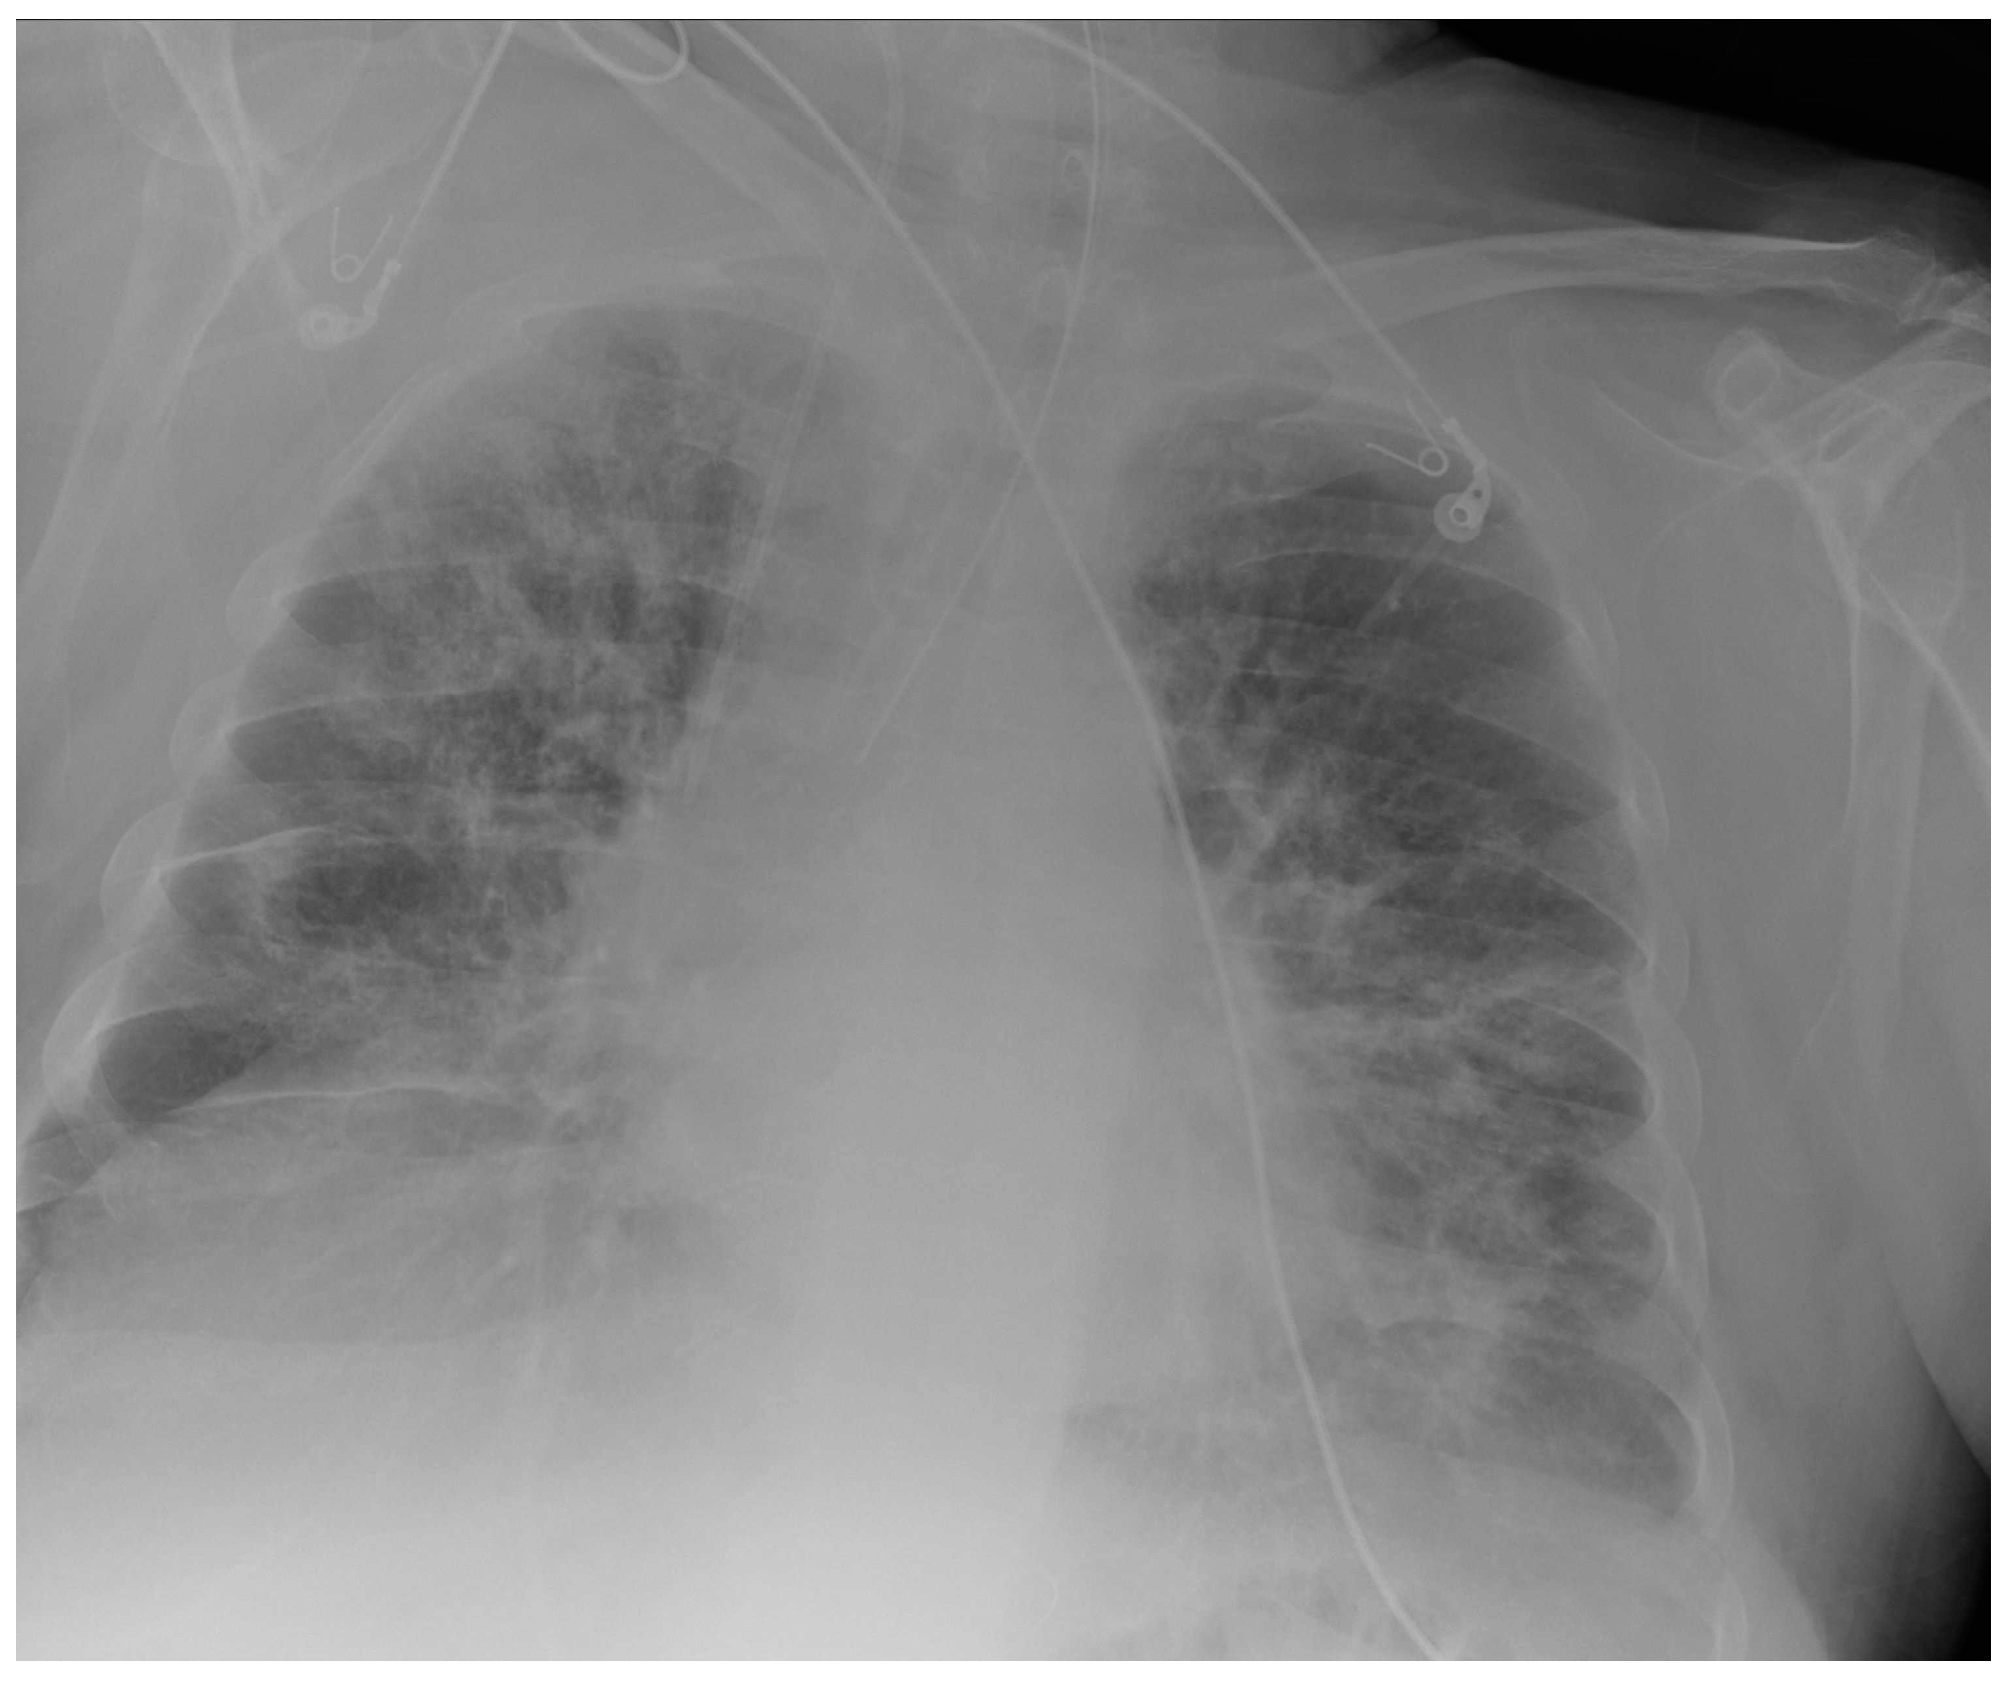

Potential confounding factors are EKGs’ leads, external tubes, artifacts and overlapping of different devices. The need to have at least two orthogonal projections to correctly locate a device can be a limit in patients in which only an anteroposterior projection is feasible. Moreover, technical factors must be considered, such as the orientation of the X-ray tube and patient rotation (Figure 1) [2].

Figure 1.

Potential confounding factors when checking for devices on a CXR. (a) Anteroposterior CXR of a right-sided rotated patient can simulate the dislocation of the central venous catheter (white arrows). (b) Anteroposterior CXR of a patient with multiple devices and external EKG leads.